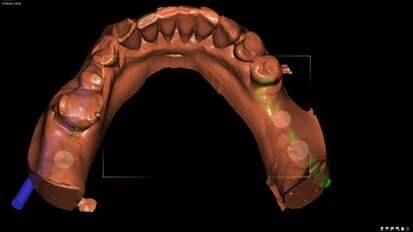

Cyfrowe techniki projektowania w estetycznych ostatecznych uzupełnieniach implantoprotetycznych

W artykule opisano wykorzystanie pozycjonomera – szablonu nazębnego do ustalenia prawidłowej angulacji wszczepu wykonanego na podstawie skanu ...

zapisz